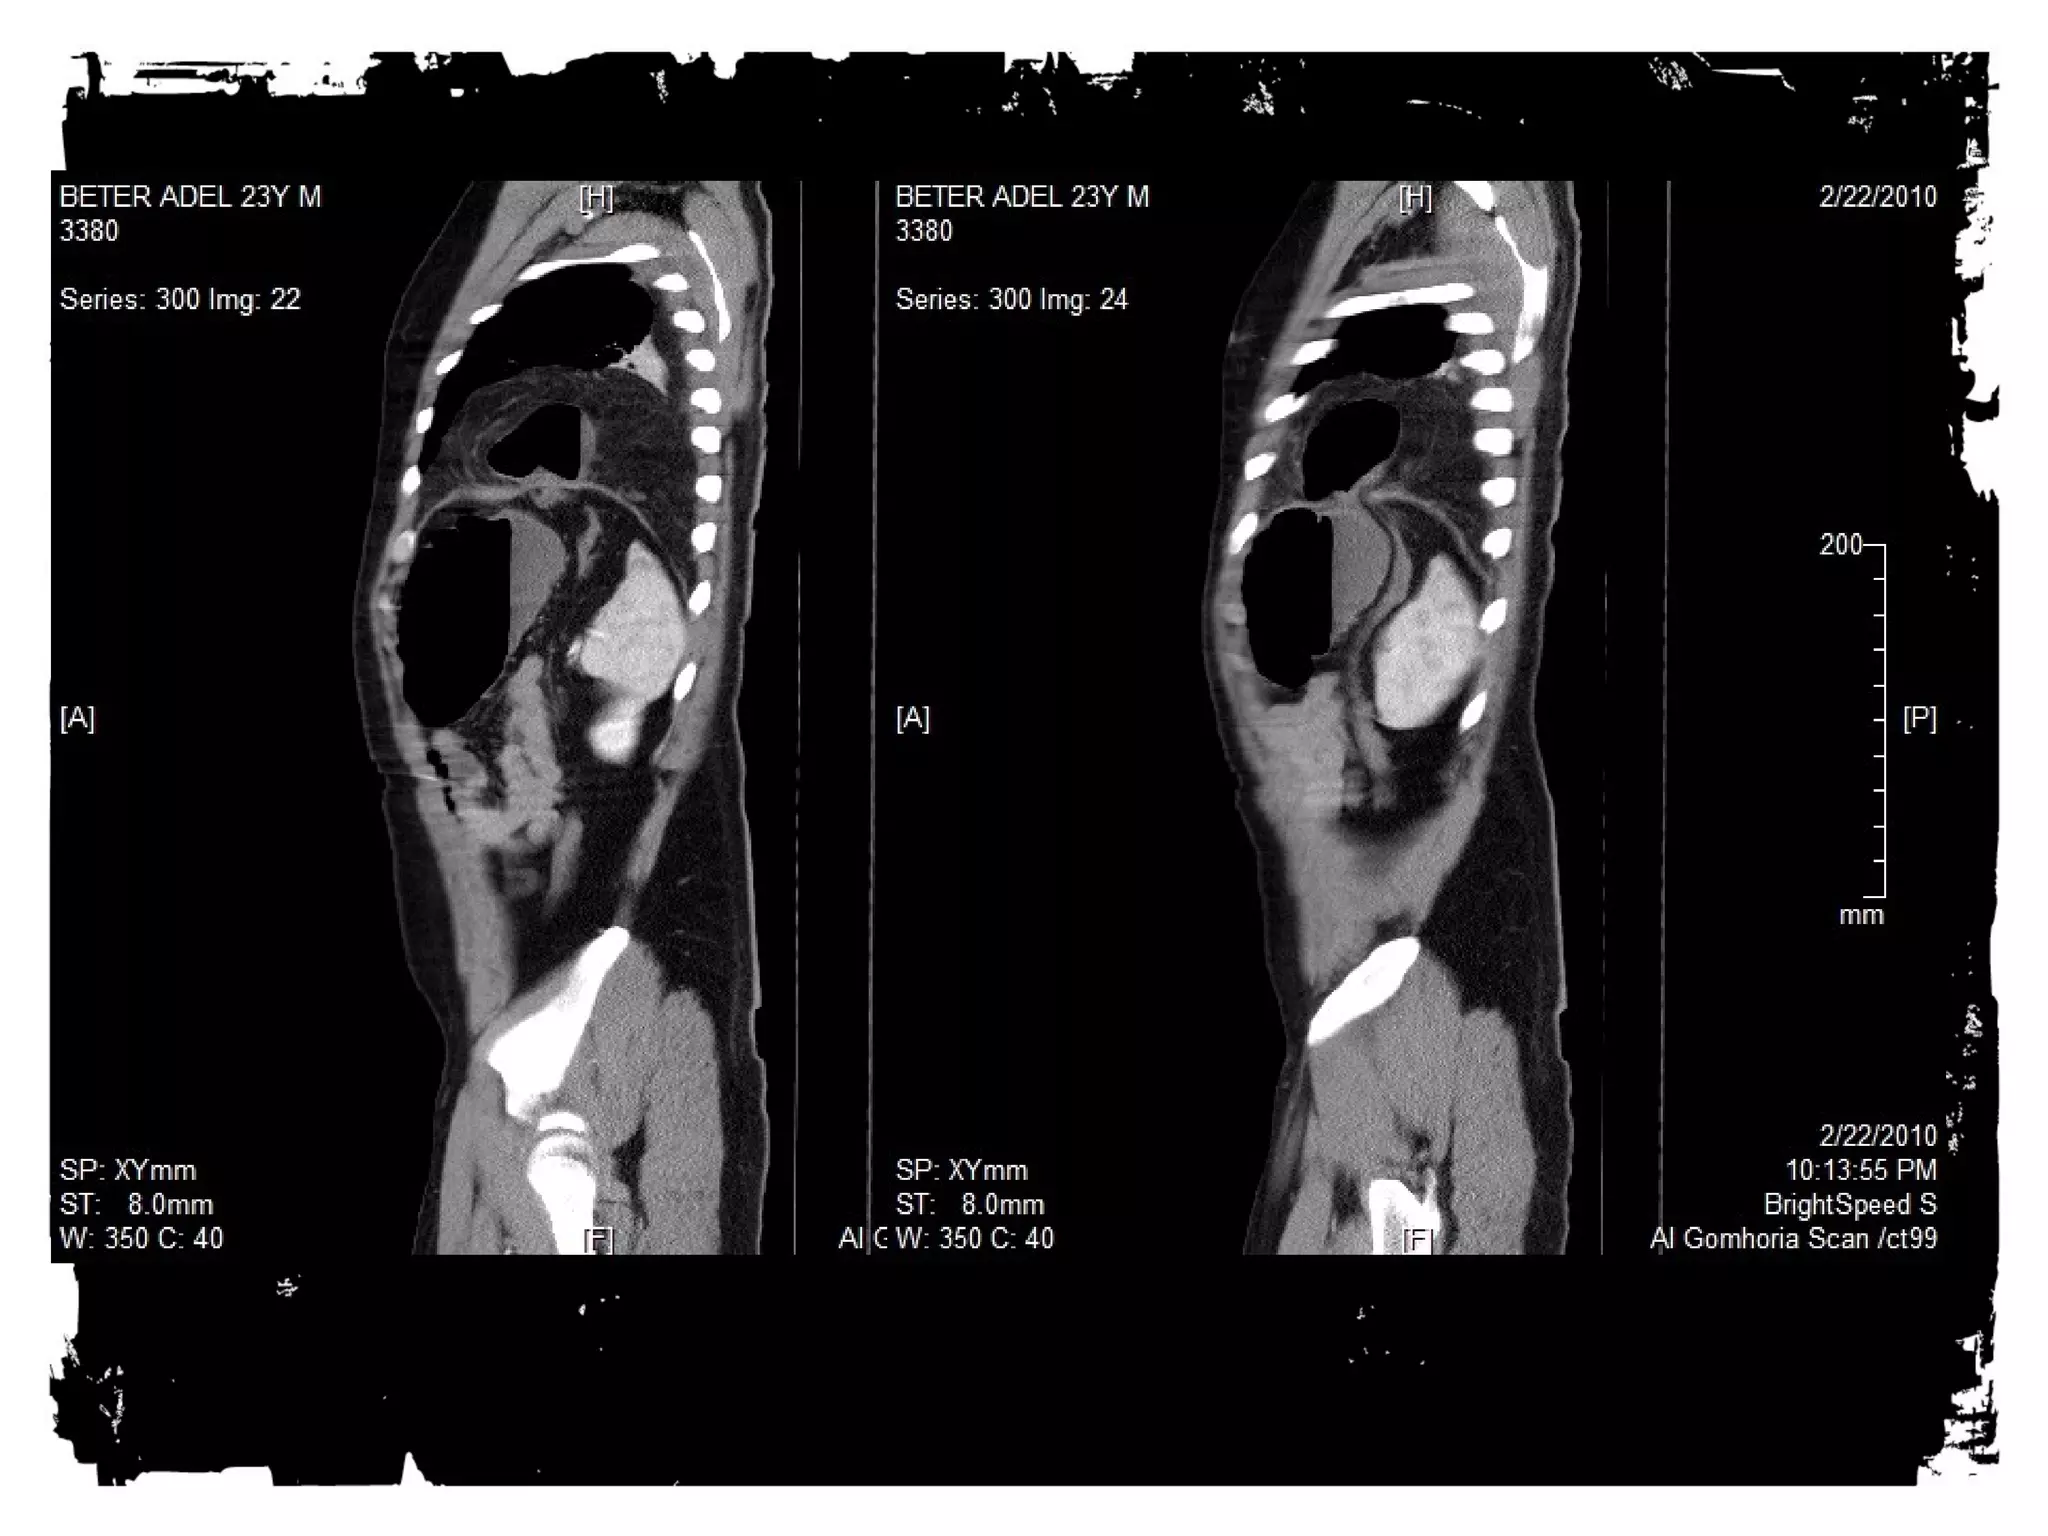

After chest trauma, imaging plays a key role for both,

the primary diagnostic work-up, and the secondary

assessment of potential treatment. Despite its well-known

limitations, the AP chest radiograph remains

the starting point of the imaging work-up. Adjunctive

imaging with CT, that recently is increasingly often

performed on MDCT units, adds essential

information not readily available on the CXR. This

allows better definition of trauma-associated thoracic

injuries not only in acute traumatic aortic injury, but

also in pulmonary, tracheobronchial, cardiac,

diaphragmal, and thoracic skeletal injuries.

• Spine Injuries

• Look for loss of

alignment, fractures and

paraspinal hematoma.

• The findings may be very

subtle.

• CT is the imaging

modality of choice for

evaluation of these

injuries.